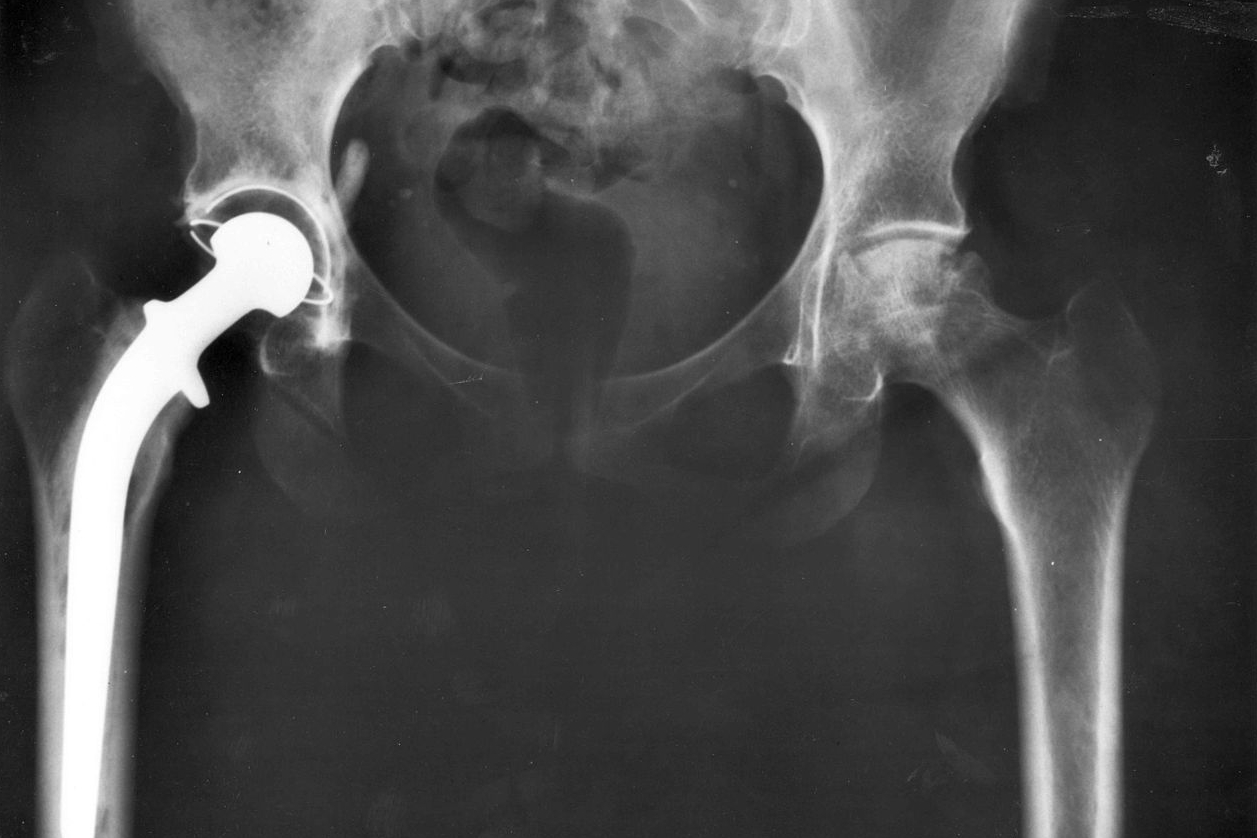

As a group of intrepid Swiss researchers point out, after total hip arthroplasty, i.e. a hip replacement surgery, the “relative risk of prosthetic or bony impingement and joint instability during sexual activities” is quite unknown. Nor do we know exactly what kind of range of hip motion is required for different sexual positions.

But thanks to two brave volunteers, our world of knowledge just got quite a bit wider. The young, healthy subjects, one male and one female, came into the lab and performed 12 common sexual positions recorded through motion capture. Both underwent an MRI scan to construct 3-D models of their pelvises and femurs, and the images were analyzed for any dangerous hip movement. Then reflective markers were attached to their skin with double-sided tape to track the movement of their bodies in each position. Not sure how much actual fun they had, as the paper says they were asked to “simulate the motion,” and doesn’t go into detail as to what “performing” the positions entailed. They went through each position three times. And, for the sake of curiosity and rigorous science: “A mattress was utilized and a standard 45 cm height stool was used for the position requiring a chair.”